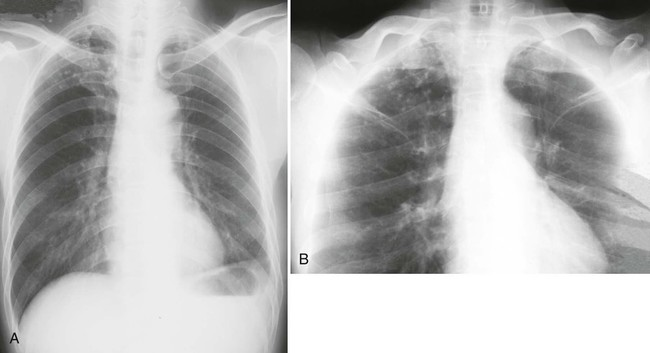

chest AP lordotic projection 會讓鎖骨飛上去,如下圖,左邊是正常的chest PA view、右邊是chest lordotic view,chest PA影像中,鎖骨都會擋住一部分的上肺葉,chest lordotic影像中,鎖骨就不會擋住上肺葉,可以觀察到鎖骨後的肺部區域。